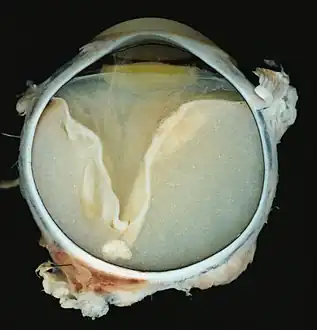

Grossly, retinal detachment and yellowish subretinal exudate containing cholesterol crystals are commonly seen. Microscopically, the wall of retinal vessels may be thickened in some cases, while in other cases the wall may be thinned with irregular dilatation of the lumen.[10] The subretinal exudate consists of cholesterol crystals, macrophages laden with cholesterol and pigment, erythrocytes, and hemosiderin.[11] A granulomatous reaction, induced by the exudate, may be seen with the retina.[12] Portions of the retina may develop gliosis as a response to injury.

A case of Coats' disease, showing total retinal detachment with subretinal exudate containing cholesterol crystals and a fibrous nodule in the posterior pole -